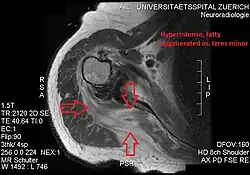

Conjoint and intact tendon disc of teres minor and infraspinatus muscle

Intact teres minor tendon with physiologically hypointense signal

Hyperintense, fatty degenerated teres minor muscle

Ultrasonography is a tool to detect a fatty degenerative atrophy of the teres minor and shows in affected muscles increased echogenicity and betimes a slight reduction in muscle bulk. MR imaging helps to consolidate the diagnosis of neurogenic muscle atrophy. Extracellular edema after traumatic events causing neural damage show an increased signal intensity on T2-weighted MRI sequences and normal intensity on T1-weighted sequences. Posterior humeral circumflex artery compression and reduced blood flow in stressful arm positions and or maneuvers can be diagnosed by a Doppler ultrasonography. The nerve should be detected adjacent to the vessel. In an elevated arm position the axillary neurovascular bundle can be seen at the posterior axillary fold just before it perforates the deltoideus, while the posterior course is well visible in the neutral position. For a detailed assessment of the artery, a MR angiography is required. The major task of an ultrasonographic examination is to rule out any space occupying mass. Additional electromyography is helpful to reveal any decelerated nerve conduction velocity, and thus denervation of the concerned muscle.[5]